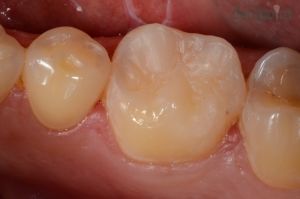

Esztétikus fogtömés készítése

Savas refluxtól szenvedő páciensünk őrlőfoga sajnos erőteljes kopásnak indult, azonban kompozit tömőanyaggal sikerült tökéletesen helyreállítani a sérült fogat!

Fogtömés: Dr. Suskó Ivett

1) Rágófelszín kopása

2) Esztétikus fogtömés